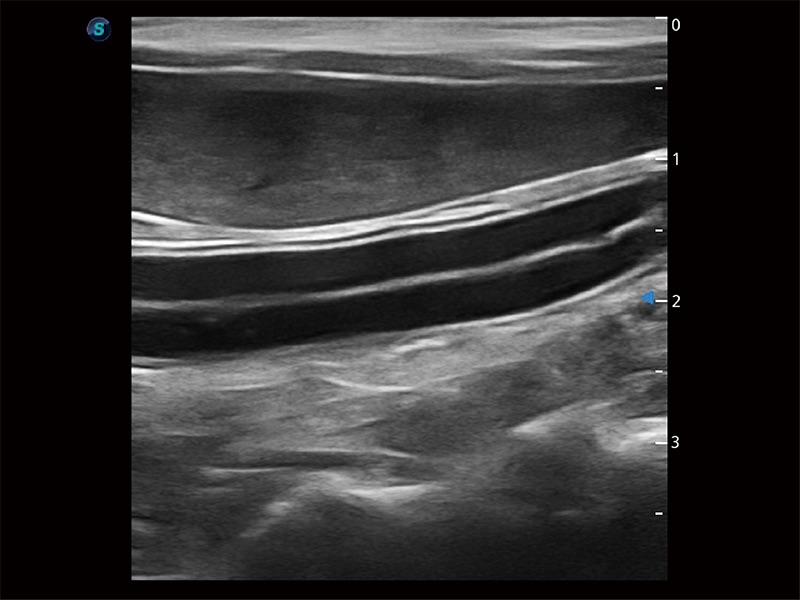

极大提升超低速微细血流的检出能力,同时更精准地滤除软组织和超声信号,为兽用医生提供以往无法通过常规血流获得的疾病诊断信息。

为精细结构及组织边缘提供高清晰度的图像和更大的成像视野。帮助减轻医生的用眼疲劳,快速精准获得测量的数据。